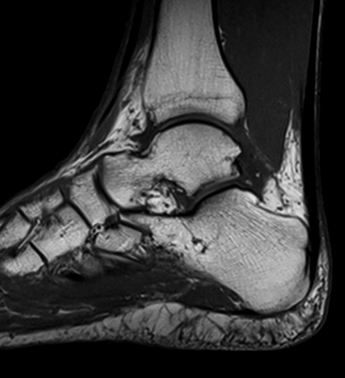

La Resonancia magnética (RMN) es un método de imagen multiplanar no invasivo, basado en la interacción entre la radiofrecuencia, los campos magnéticos y ciertos núcleos en el cuerpo humano (generalmente núcleos de hidrógeno del agua), después que el cuerpo ha sido introducido en un campo magnético fuerte. La información obtenida es procesada por un ordenador y transformada en imágenes del cuerpo humano.

La RM consigue información sobre la estructura del cuerpo permitiendo diferenciar entre tejidos normales y anormales lo que la convierte en una técnica muy sensible para detectar enfermedad. Esta sensibilidad está basada en un alto grado de contraste debido a las variaciones en las propiedades de relajación magnética de los diferentes tejidos, tanto normales como anormales.